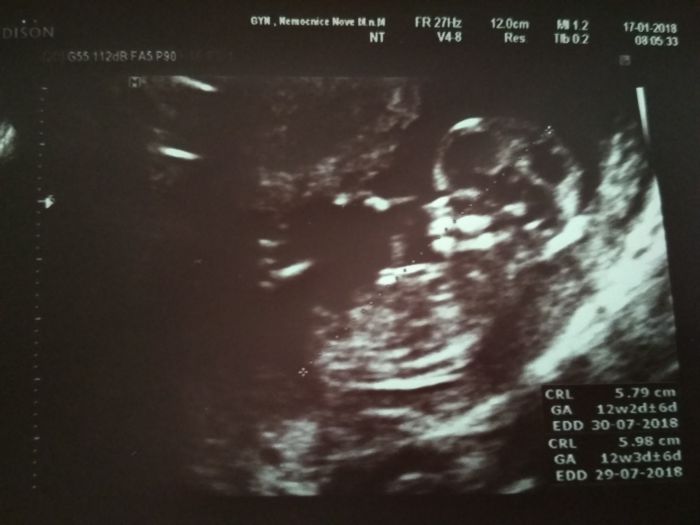

Tak my jsme dnes byli s manželem taky na screeningu, všechno vypadá normálně bez vad. Další kontrola u své MUDr. až za měsíc. Od pondělí už můžu pracovat, tak konečně mi to začne utíkat. Zatím nic nepořizujeme, sem tam se podívám na kočárek, ale času je ještě mooooc :-)